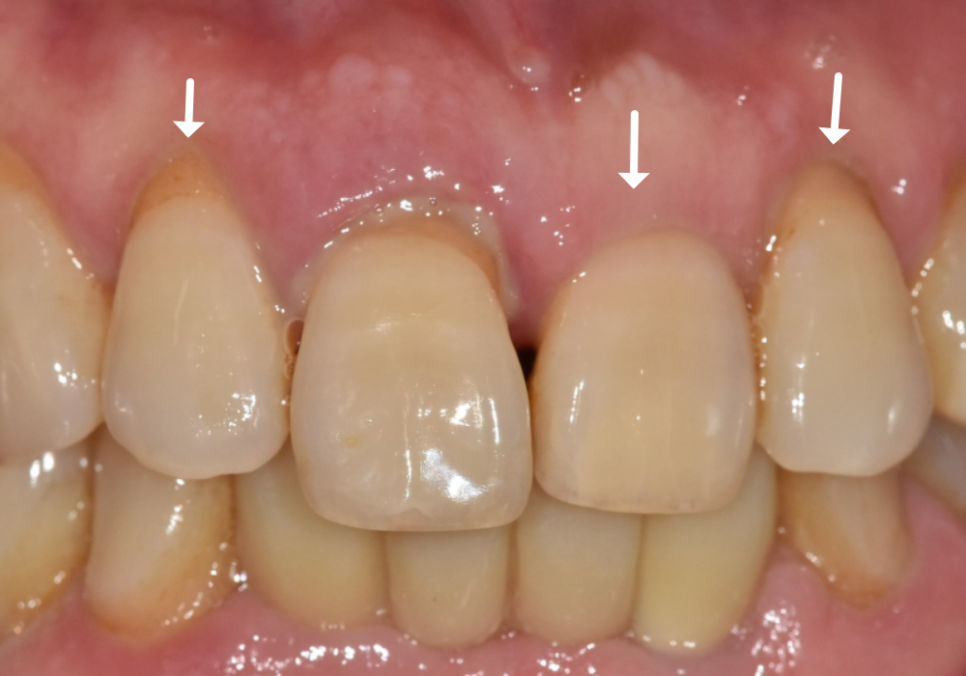

방사선 사진을 살펴보니,

옆 치아들에 비해 잇몸뼈가 많이

낮아진 걸 확인할 수 있었습니다.

이 정도의 염증이라면 양옆에 치아도

안전할 수 없는 상황...

아니나 다를까.

양옆의 치아들도 조금씩 흔들림이 진행되고 있었습니다.ㅜㅜ

하지만 양옆 치아들은 가운데 앞니보다 뼈 상태가

비교적 나은 상황이라

이대로 뽑기에는 아쉬움이 따르더라고요~